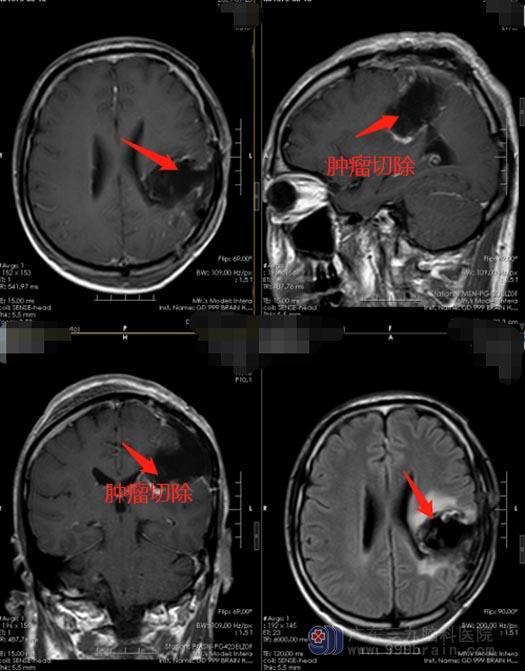

排除手术禁忌症后,鲁明带领团队在唤醒麻醉下为刘先生行“左颞顶叶复发胶质瘤切除术”,手术过程顺利,术后刘先生神志清醒,活动正常。术后病理检查报告:低级别胶质瘤,考虑为节细胞胶质瘤,WHO I级。